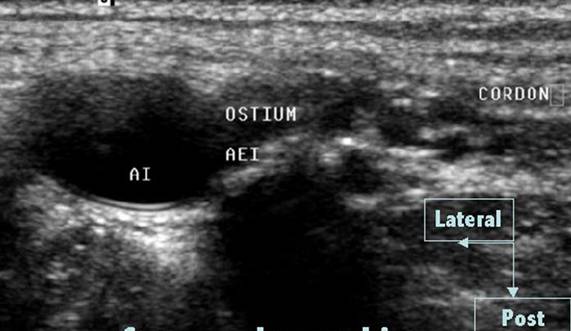

In plan eco anatomic, orificiul inguinal profund corespunde ostiumului arterei epigastrice inferioare, ramura a arterei iliace externe. La acest nivel emerge cordonul spermatic deci elementele constitutive diverg (fascicolul spermatic si canalul deferent).

Reperul ecografic esential al orificiului inghinal profund este ostiumul arterei epigastrice inferioare

La nivelul ostiumului arterei epigastrice inferioare, cordonul spermatic vizulizat imediat inspre inauntru, sub forma unei structuri ovalare, multi-foliculare.